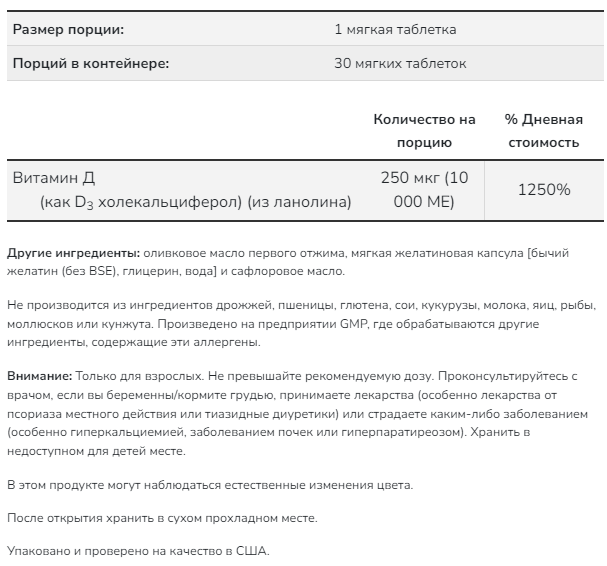

Размер порции: 1 мерная ложка (прибл. 5,15 г)

Порций в упаковке: прибл. 40

- Количество в 1 порции: % от суточной нормы

- Витамин C (в виде аскорбата кальция) 90 мг 100%*

- Гидролизованные пептиды из рыбьего коллагена 5000 мг †

- Гиалуроновая кислота (в виде гиалуроната натрия, неживотного происхождения) 60 мг †

- * Процент от суточной нормы при условии потребления 2000 калорий в день. † Суточная норма не определена.

- 5,12 г — среднее значение. Фактически 1 мерная ложка может вмещать немного меньше или немного больше, чем 5,12 г.

Другие ингредиенты

Гидролизованные пептиды из рыбьего коллагена, витамин C (в виде аскорбата кальция), гиалуроновая кислота (в виде гиалуроната натрия, неживотного происхождения)

Содержит рыбу (один или несколько из видов: треска, пикша, хек, тилапия).

При производстве данного продукта не используются молоко, яйца, моллюски и ракообразные, древесные орехи, арахис, пшеница, соя и глютен. Производится на предприятии, проходящем независимые проверки и имеющем сертификацию cGMP, где могут обрабатываться другие продукты, содержащие данные аллергены и ингредиенты.